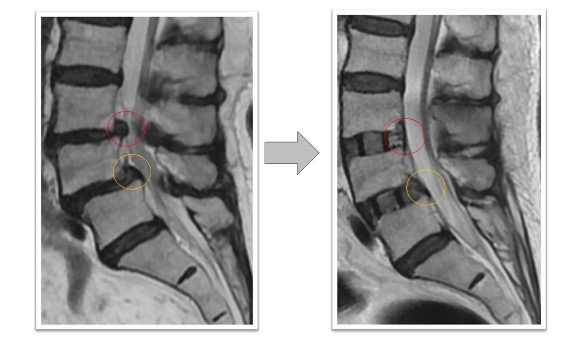

頚椎固定術実例(*患者様の許可を得て掲載しています)

頚椎症性椎間孔狭窄、椎間板ヘルニア、頚椎後湾

両上肢から肩にかけての痛み、頸部痛の患者様に対してC4/5/6の頚椎前方固定術を実施しました(赤丸)。術後には狭小化していた椎間高が回復し、さらに術前には同部位で頚椎の後弯(頚椎が後ろに凸となり頭が前に下がる状態)が認められていましたが、術後は頚椎の並び(アライメント)が改善しています。また、同時にこの断面では見えていませんが椎間孔も上下に拡張することで術後にあった肩から上腕への痛みが術後消失しています。